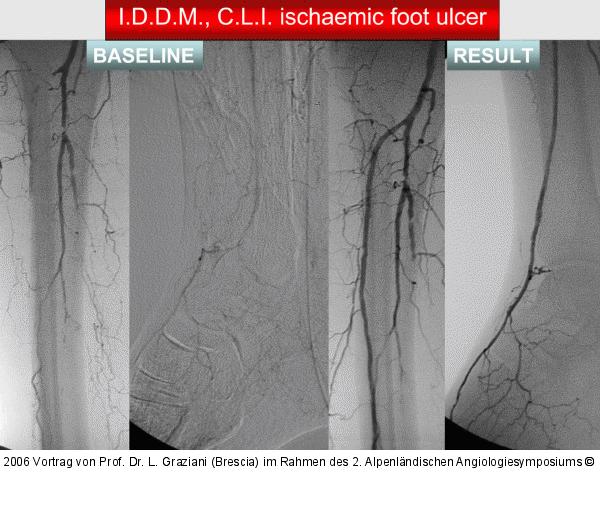

Vortrag von Prof. Dr. L. Graziani (Brescia) im Rahmen des 2. Alpenländischen Angiologiesymposiums

PTA of the foot arteries in diabetics: Extremities Extreme Angioplasty

Abbildung 20: Revaskularisation